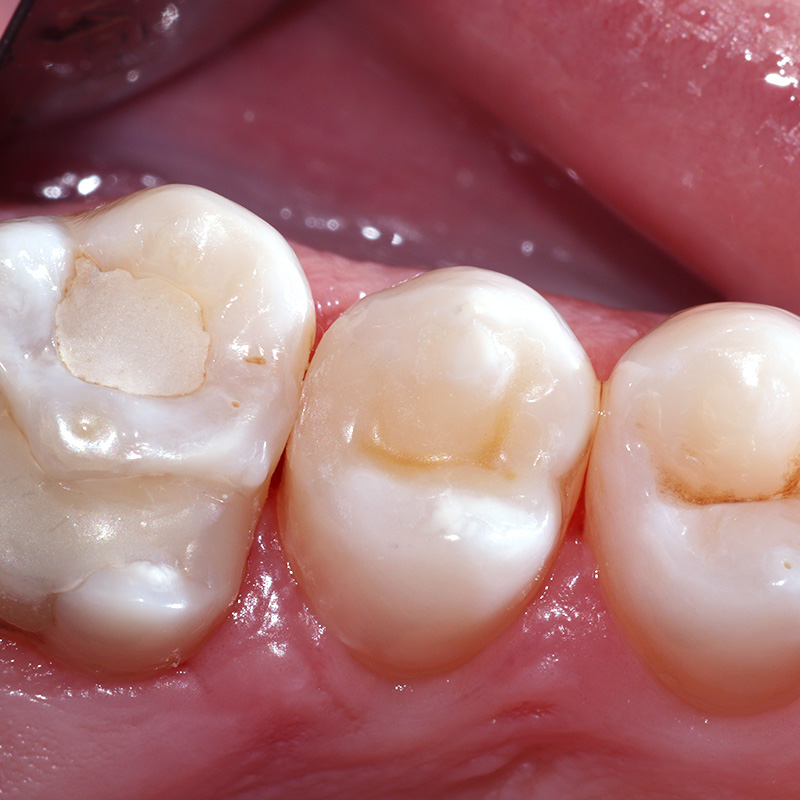

До и после лечения

Пациент обратился в «Стоматологию Комфорта» с жалобами на постоянное застревание пищи между зубами верхней челюсти с правой стороны. После осмотре стоматолог Галухина Карина Николаевна обнаружила кариес дентина зуба 1.6 и поставила соответствующий диагноз. Врачом было принято решение о проведении лечения с применением фотополимерного композита Estelite.

В ходе лечения проведены следующие работы:

- введение анестетика;

- механическая и медикаментозная обработка зуба 1.6 под контролем кариес-маркера;

- наложение лечебной прокладки;

- наложение изолирующей прокладки;

- пломбировка зуба композитом Estelite.